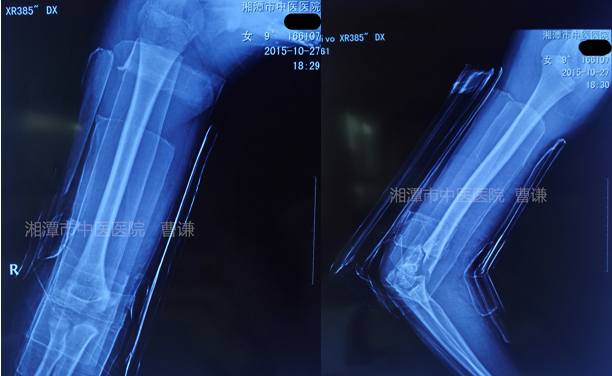

下面我們來看一例典型病例,患者:女,9歲,跌倒致右肘部畸形、腫痛、活動受限,就診于我院,拍片診斷為Gartland 型肱骨髁上骨折。入院行楊氏四步復(fù)位法手法整復(fù),小夾板外固定。入院拍片如下: